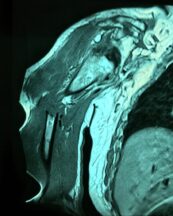

Angioresonancia periférica (miembro superior derecho).

Pacientes con luzación glehumeral anterior y fractura diafisiaria del humero, de un mes de evolución. Se complica con una oclusión de un segmento de la arteria subclavia-axilar, secundaria a trombosis.

Las lesiones de vasculares asociadas a fracturas y luxaciones del hombro son poco frecuentes, aunque potencialmente muy graves por lo que requieren un diagnóstico y actuación urgentes. Debido a la proximidad anatómica, pueden coexistir signos de compromiso de nervios mediano, radial y cubital.